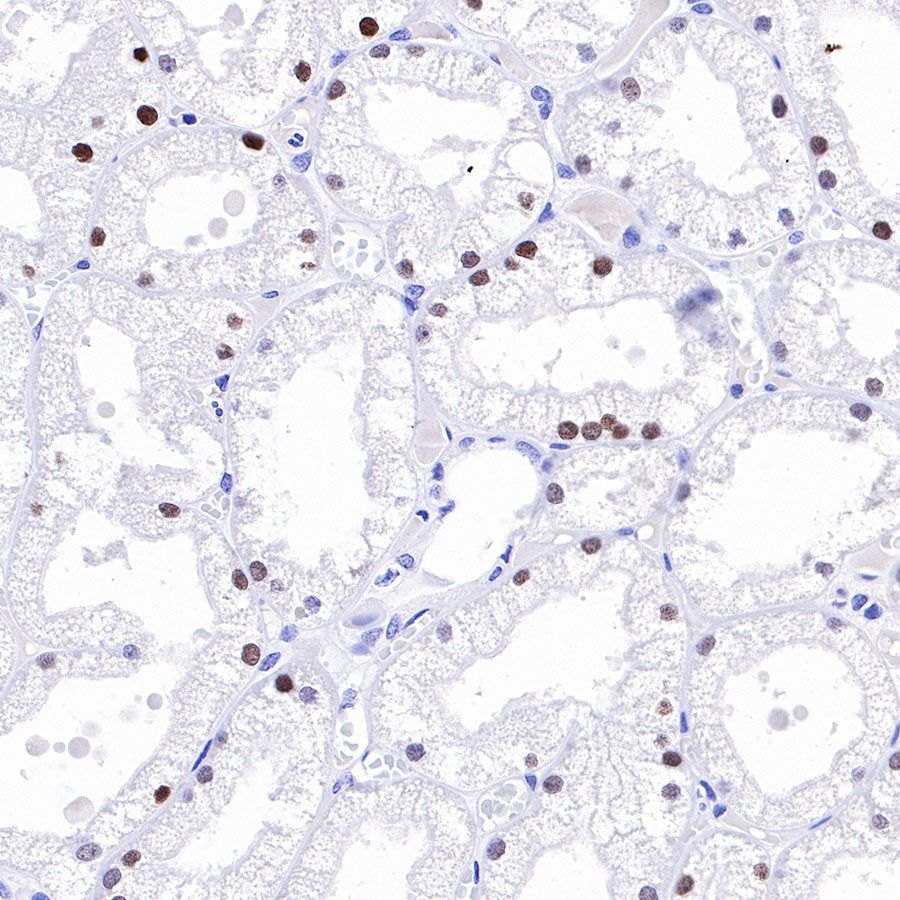

IHC shows positive staining in paraffin-embedded human kidney. Anti-HNF4α antibody was used at 1/500 dilution, followed by a HRP Polymer for Mouse & Rabbit IgG (ready to use). Counterstained with hematoxylin. Heat mediated antigen retrieval with Tris/EDTA buffer pH9.0 was performed before commencing with IHC staining protocol.

IHC shows positive staining in paraffin-embedded rat kidney. Anti-HNF4α antibody was used at 1/500 dilution, followed by a HRP Polymer for Mouse & Rabbit IgG (ready to use). Counterstained with hematoxylin. Heat mediated antigen retrieval with Tris/EDTA buffer pH9.0 was performed before commencing with IHC staining protocol.